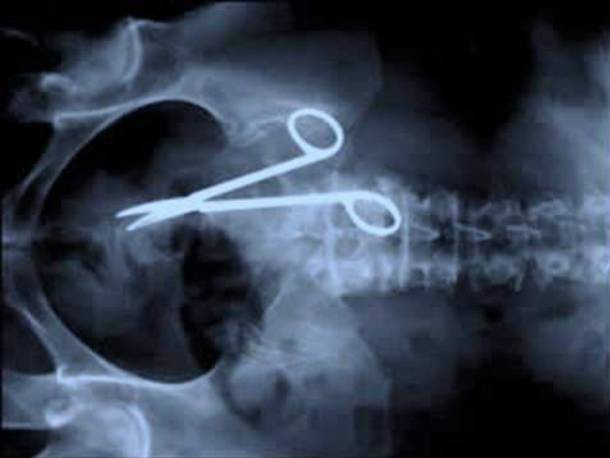

5. Quên kéo trong bụng bệnh nhân: truyền thuyết là có thật!

Khi chị Pat Skinner quay lại bệnh viện 18 tháng sau một cuộc phẫu thuật để than phiền là dạo này bụng cứ nhâm nhẩm đau, các bác sĩ đã chụp X-quang và nhanh chóng phát hiện ra ngày xưa bị mất một cái kéo phẫu thuật, tìm mãi không thấy đâu, thì ra là đã nhờ chị Pat cất hộ...